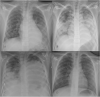

Pediatric chest x-ray in covid-19 infection

Results: Median age was 79.8 months (ranging from 2 weeks to 16 years of age). Fever was the most common symptom (43.5 %). 90 % of CXR showed abnormalities. Peribronchial cuffing was the most common finding (86.3 %) followed by GGOs (50 %). In both cases central distribution was more common than peripheral. Consolidations accounted for 18.1 %. Normal CXR, pleural effusion, and altered cardiomediastinal contour were the least common.

Conclusion: The vast majority of CXR showed abnormalities in children with COVID-19. However, findings are nonspecific. Interobserver correlation was good in describing consolidations, normal x-rays and GGOs. Imaging techniques have a role in the management of children with known or suspected COVID-19, especially in those with moderate or severe symptoms or with underlying risk factors.